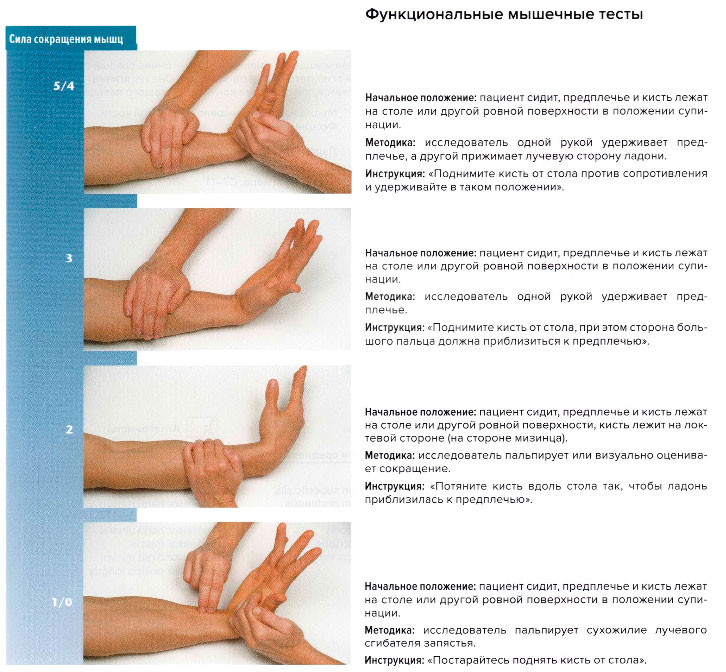

Ладонное сгибание кисти. Функциональные мышечные тесты[править | править код]

Проблемы и комментарии

- Длинная ладонная мышца считается вспомогательной при ладонном сгибании кисти, которое в основном выполняется локтевым и лучевым сгибателями запястья.

- Сгибатели кисти, которые можно пропальпировать (от лучевой стороны к локтевой):

- m. flexor pollicis longus;

- m. flexor carpi radialis;

- m. palmaris longus;

- m. flexor digitorum superficialis;

- m. flexor carpi ulnaris.